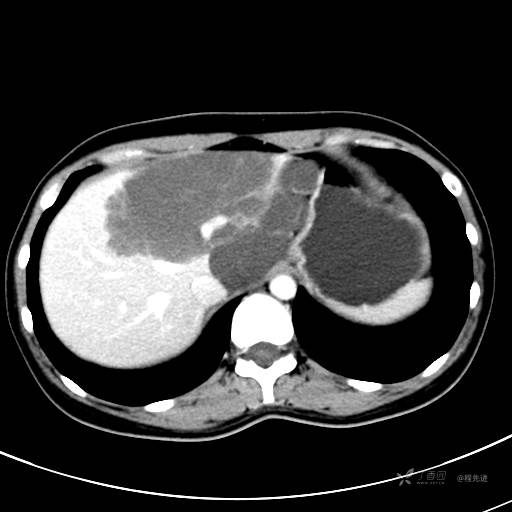

CT平扫+增强,每个序列3张图

CT值 平扫48HU 动脉期66HU 静脉期68HU 延迟期62HU